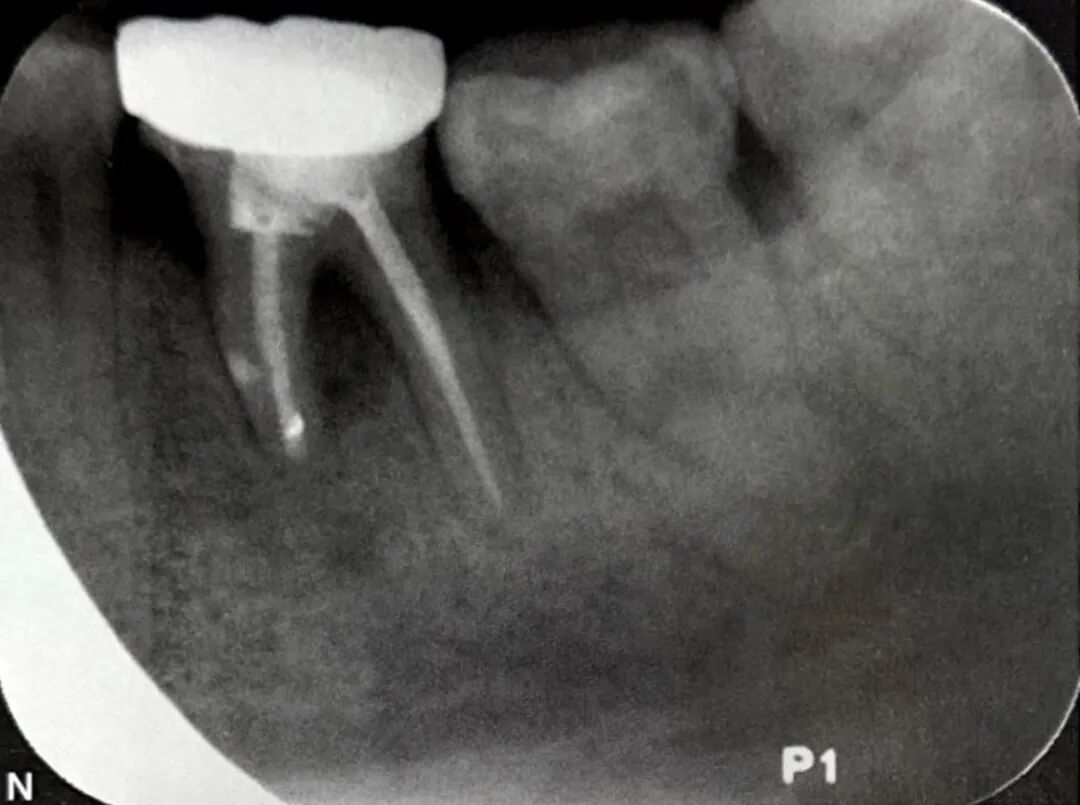

导致根旁牙槽骨破坏的可能病因有根裂、侧支根管、根折、根旁囊肿、牙骨质撕裂等。当根管侧支位于牙根中段时,感染破坏根周牙槽骨,可形成类似根裂的影像学特点,如图3所示,A为口内像颊侧面观,示左下颌第一磨牙近中近龈缘处牙龈窦道(箭头);B为根尖片示根管充填良好,近中根根尖以及根周大范围透射影,波及根分叉区;C为CBCT矢状位;D为CBCT冠状位;E为CBCT水平位,近中根根尖、根周以及根分叉区骨质破坏;F为左下颌第一牙行显微根尖外科手术,切开翻瓣牵拉 ;G为根尖周刮治和根尖切除;H为探查,近中根未见根裂线,近中面中段见根管侧支(箭头);I为主根管和根管侧支逆行预备和充填;J为术后根尖片,可见根管侧支(箭头);K为术后2个月随访根尖片;L为术后4个月随访根尖片;M为术后7个月随访根尖片;N为术后24个月随访根尖片,根周和根尖周完全愈合。